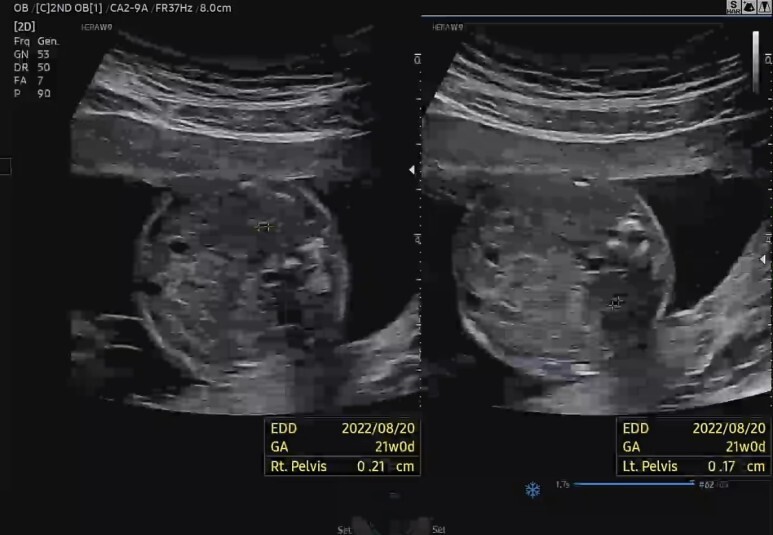

음.. 이건 양쪽 신장인듯? (PELVIS)